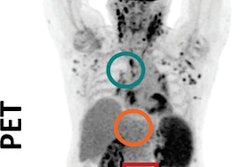

SSTR PET reflects higher Krenning scores than In-111 pentetreotide in low-volume disease. The patient was graded as having a Krenning score of 4 on SSTR PET (A) but 0 on SPECT (B, C, and D) and planar imaging (E). MIP = maximum-intensity projection. Images courtesy of JNM.The retrospective study included 150 patients with suspicion or biochemical evidence of neuroendocrine tumors who underwent both Ga-68 DOTATATE PET/CT and In-111 pentetreotide imaging with planar scintigraphy and SPECT within one week. Three readers independently graded the images using the Krenning score based on the lesion with the highest uptake. The volume and extent of tumor burden, lesion size, and maximum standardized uptake value (SUVmax) were also compared with the Krenning scores.